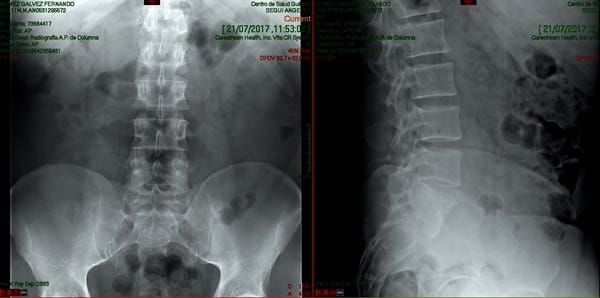

Esta es la ultima radiografía que tengo, según mi medico de cabecera la cosa esta complicada y tengo que pasar por el quirófano, a sabiendas de que sera incapacitante, tengo 37 años y ya no puedo más con el dolor, sin embargo el especialista que me a tocado me dice que no que aguante .